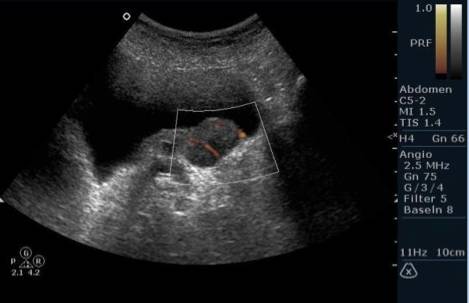

Диагностика

Обнаружить тяжи в амниотической жидкости можно с помощью ультразвукового исследования, которое проводится в начале второго триместра, хотя это не всегда удается. Нити могут быть настолько тонкими, что их сложно заметить на экране. Если у ребенка впоследствии будут выявлены деформации частей тела, то устанавливается соответствующий диагноз.

Если потребуется провести дополнительные исследования, то может быть назначено 3D-УЗИ, МРТ и эхокардиография плода. Эти процедуры необходимы для предотвращения серьезных последствий для здоровья малыша.